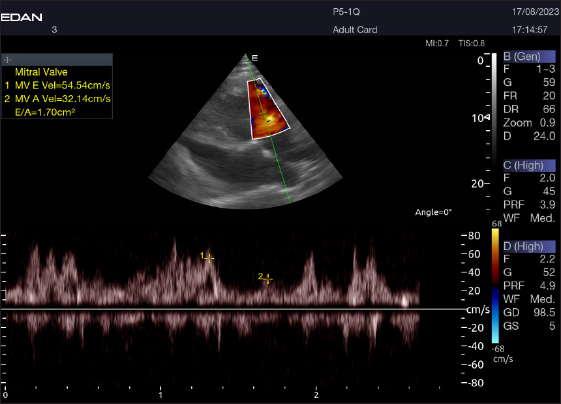

Doppler echocardiography

Table 4 provides an overview of pulsed-wave Doppler echocardiographic serial measures in adult racing camels. The pulsed-wave Doppler echocardiographic measurements’ mean values ± standard deviation were recorded for Tv E/A (1.3 ± 0.2 cm2), Mv E/A (1.3 ± 0.2 cm2), Av max (−88.2 ± 25.1 cm/second), and Pv max (−59.2467 ± 17.4 cm/second), as shown in Table 4.

Left parasternal ultrasonography

The Mv E/A (Fig. 8), Tv E/A (Fig. 9), and maximum velocity of the aortic valve (Av Vmax) (Fig. 10) were all measured using pulsed-wave Doppler at LPSLAx in all camels. Two cases were observed with mild mitral regurgitation detected through continuous-wave Doppler, but the regurgitation was not considered significant (Fig. 11).

Fig. 8. Left parasternal longitudinal axis of a 16-year-old racing camel showing pulsed wave Doppler over the mitral valve (1=E wave and 2=A wave).

The pulsed-wave Doppler echocardiography of racing camels is not well documented. While all camels had their Mv E/A, Tv E/A, and maximum velocity of the Av Vmax recorded using pulsed-wave Doppler at (LPSLAx), the majority of cases (58.4%) had trouble measuring the pulmonary valve from the right short parasternal view. Using continuous-wave Doppler, minor mitral regurgitation was observed in two patients, but the regurgitation was not substantial.